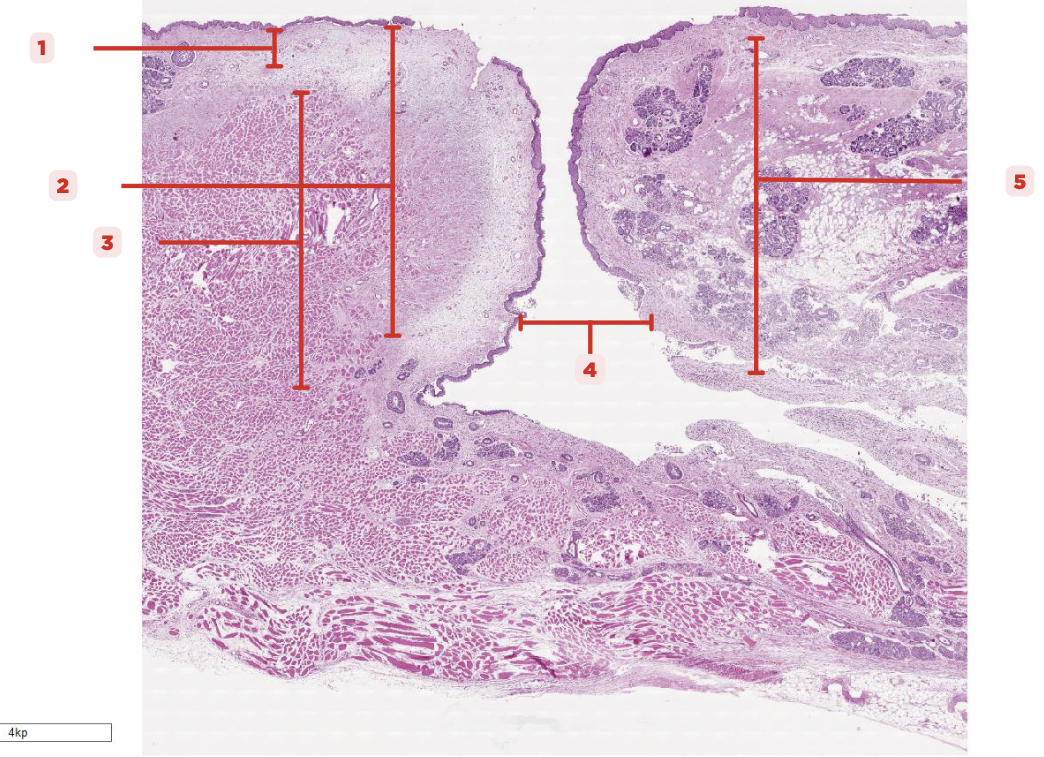

Identify the structure labeled as 1.

Laryngeal Ventricle

Space that separates the true and false vocal cords (#4)

True Vocal Cord

The #2 consists of a lamina propria that includes the vocalis ligament and a group of skeletal muscles known as the vocalis muscle.

Vocalis Ligament

Identify the structure labeled as 1.

True Vocal Cord

Identify the structure labeled as 2.

Vocalis Muscle

Identify the structure labeled as 3.

Laryngeal Ventricle

Identify the structure labeled as 4.

False Vocal Cord

Identify the structure labeled as 5.